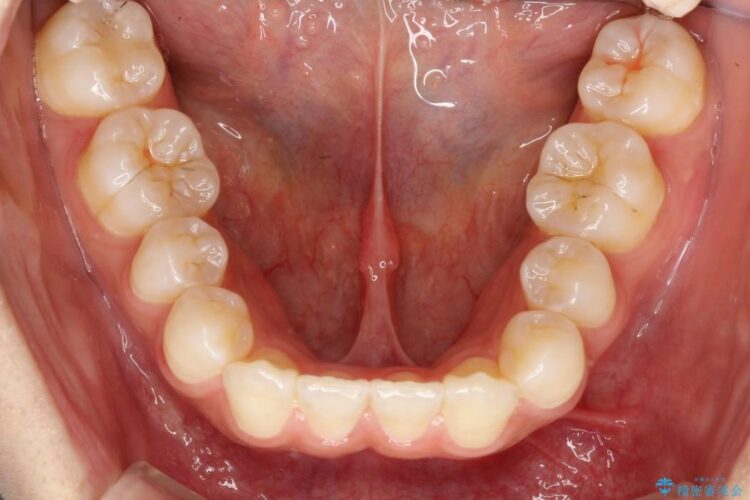

下顎の左右2番と上顎左の計3本の歯が生まれつき欠損しており、また上顎右の2番は乳歯が残っている状態でした。

レントゲン検査の結果、右上の乳歯は予後不良と判断し、上下の歯の本数のバランスを考慮して、上顎右の2番を抜歯後に矯正治療をスタートする計画にしました。

今回は乳歯を抜歯することで、上下の歯の本数がそろい、正中が一致し、バランスの良いかみ合わせにすることができました。患者様にも大変満足していただける仕上がりとなりました。